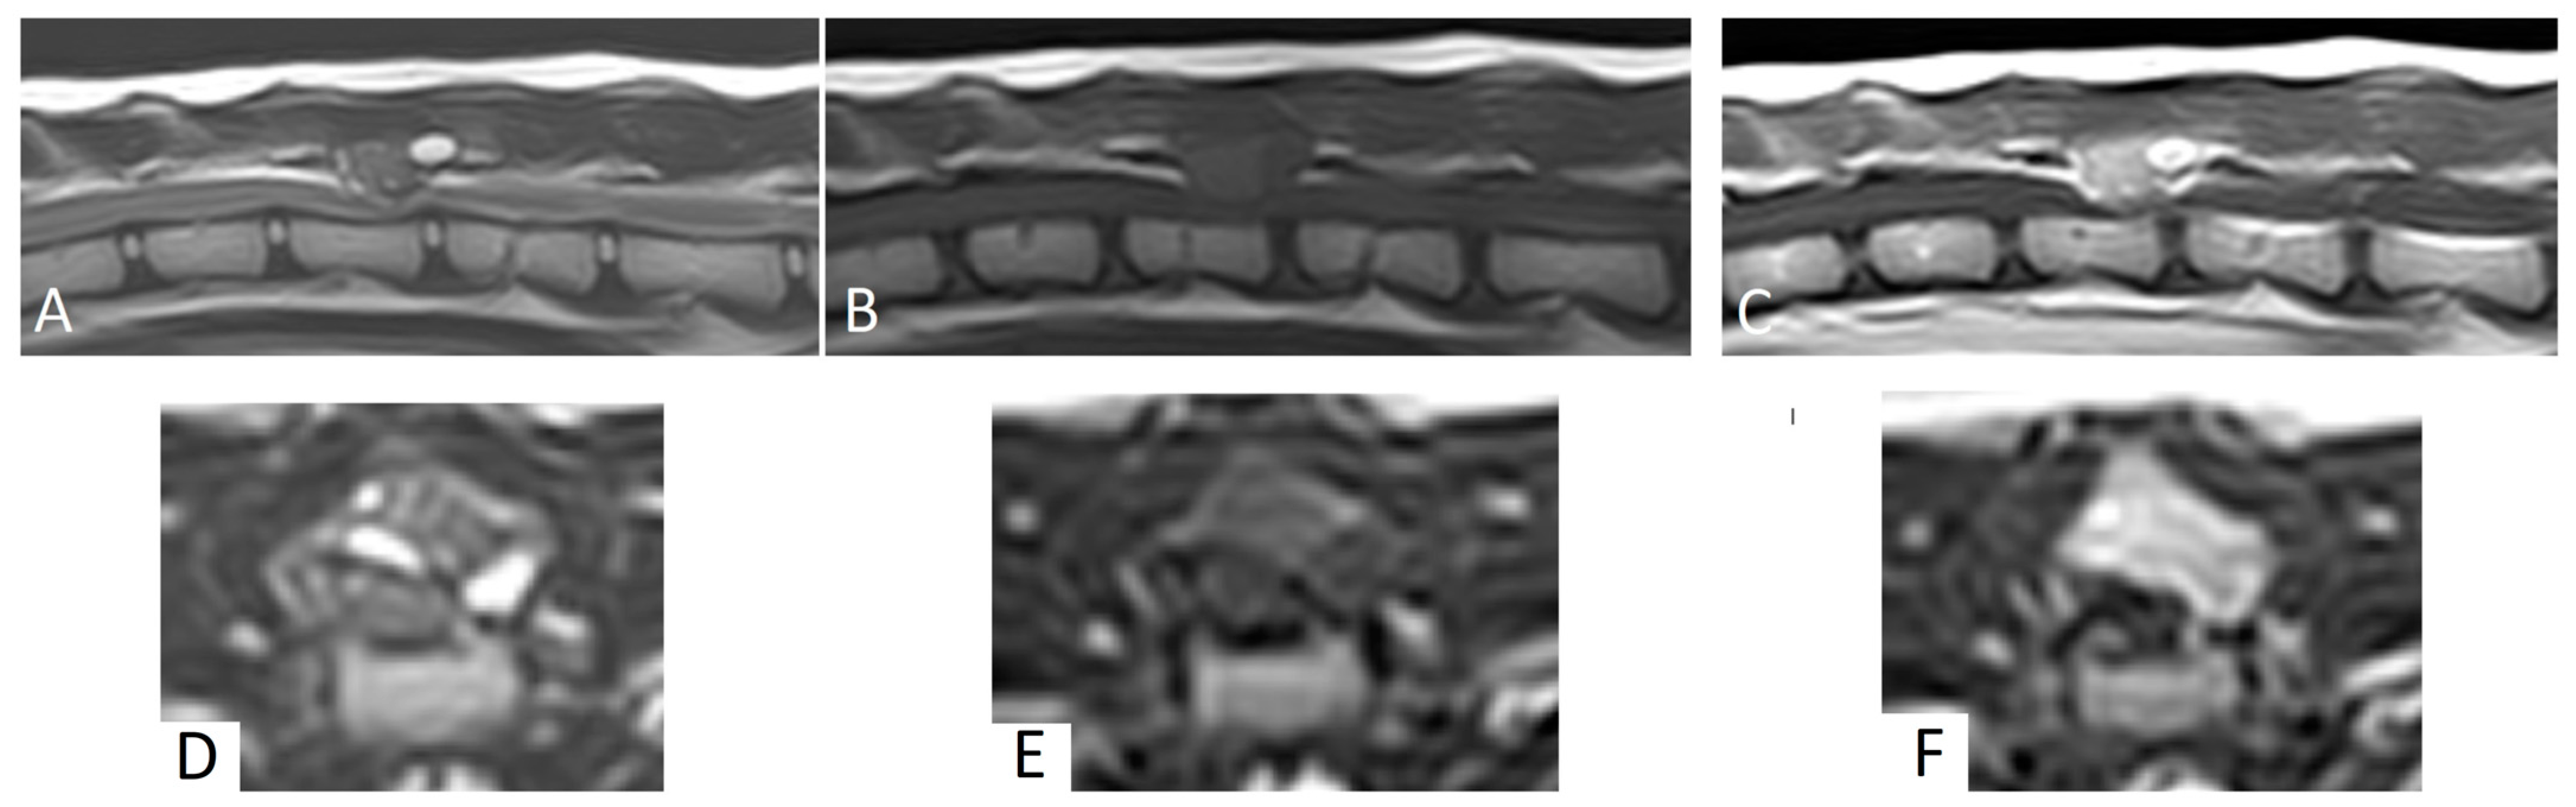

MRI revealed a 1.2 cm × 1 cm × 1.1 cm mass lesion centered on the dorsal lamina and left caudal articular process of T13, with disruption of the cortex. Relative to the spinal cord, the lesion was homogeneous and mildly hyperintense on T1W images, and heterogeneously hyperintense on T2W and STIR images (Figure 1). The mass showed strong, diffuse contrast enhancement, mainly in the areas of T2W hyperintensity (Figure 1). The mass had well-defined margins and caused moderate to severe extradural spinal cord compression. No intramedullary signal changes were seen. Based on these MRI findings, a primary bone tumor was suspected.

Figure 1. Magnetic resonance images of case 1. (AC): Sagittal plane MRI, (DF): transverse plane MRI. (A): T2W, (B): T1W, (C): T1W post-contrast, (D): T2W, (E): T1W, (F): T1W post-contrast. Note the mass lesion at the level of T13 with spinal cord compression.